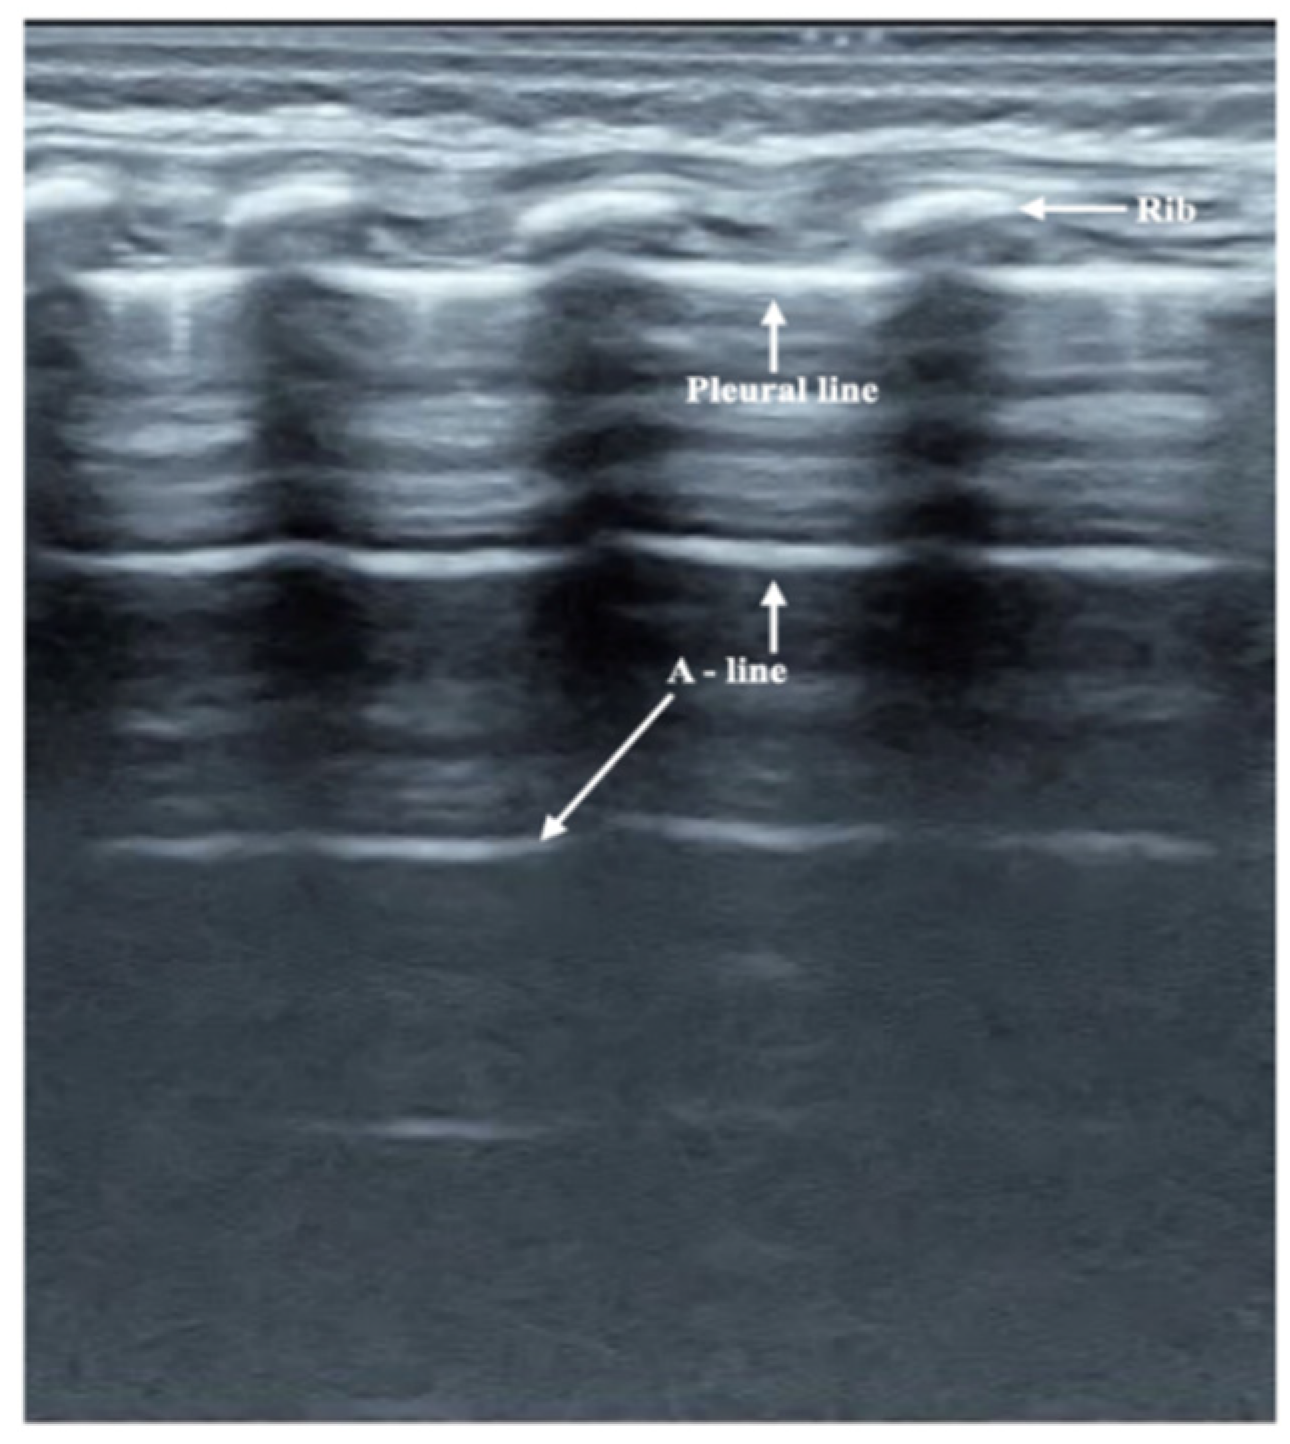

3.2. Ultrasound Manifestation of Neonatal Normal Lung